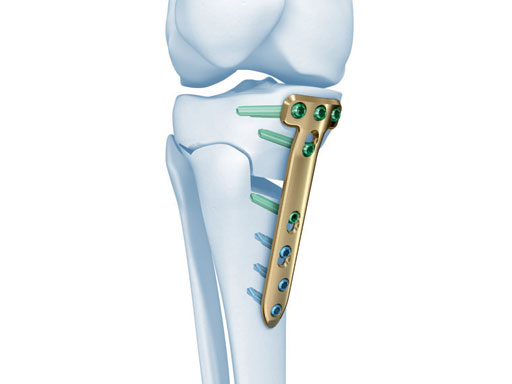

The correction is planned on a long-leg standing x-ray. After surgery, the mechanical axis should pass through a point 63% on the lateral side of the total width of the tibial plateau in the frontal plane. A transverse or slightly oblique incision is used to avoid damage to the saphenous nerve. The distal fibers of the medial collateral ligament are detached from the tibia. Under fluoroscopic control, two wires are placed in the proximal tibia marking the transverse osteotomy plane. The cut usually starts at the upper margin of the pes anserinus and ends at the tip of the fibula on the lateral side. The wires are placed exactly parallel to the tibial plateau thus taking into consideration the individual tibial slope of the patient. An incomplete cut of the posterior two-thirds of the proximal tibia is performed with an oscillating saw guided by the wires. Continuous irrigation avoids burn injury to the bone. A second osteotomy is now performed in the anterior third of the tibia in an angle of 100 ending above the patellar tendon insertion. A smaller saw blade is used and the complete anterior cortex is cut exactly in the frontal plane. The osteotomy is now gradually opened by inserting flat chisels or a spreader-chisel into the posterior osteotomy cleft. This process may take some minutes and can usually be completed without fracture of the lateral cortex. A bone spreader is now placed in the posteromedial edge of the tibia and the chisels are removed. The leg is extended and the correction is checked with the fluoroscope. A long metal rod is placed between center of the hip joint and center of the ankle joint. The projection of this rod should be at the planned point of correction on the tibial plateau lateral of the midline. Eccentric collapse of the medial joint space may cause accidental overcorrection. In this case pressure on the foot may simulate loading and body weight. The correction can be fine-tuned by opening or closing the spreader. The TomoFix Medial Tibia Plate is now placed in a subcutaneous pocket. The implant is precontoured and usually fits well to the bone surface. The distance holders avoid compression of the medial collateral ligament and the pes anserinus. Three proximal bolts are placed near the subchondral sclerosis zone. The position of the bolts is adapted to the anatomy of the proximal tibia giving optimum purchase for the bolts. An oblique lag screw is inserted distal to the osteotomy. This screw in the first combination hole allows careful compression of the lateral osteotomy hinge and pretensioning of the implant. A stab incision is created on the shaft and the implant is fixed monocortically with bolts. The lag screw and the distance holders are replaced by bolts. The medial collateral ligament is released longitudinally to reduce medial compartment pressure and the wound is closed in layers. An overflow drain may be used. Clinical and experimental work has proven that when this technique is closely followed, corrections up to and over 15 mm can be performed without bone grafting or use of bone substitutes.

A 68-year-old female.

Case provided by Alex Staubli, Luzern, CH